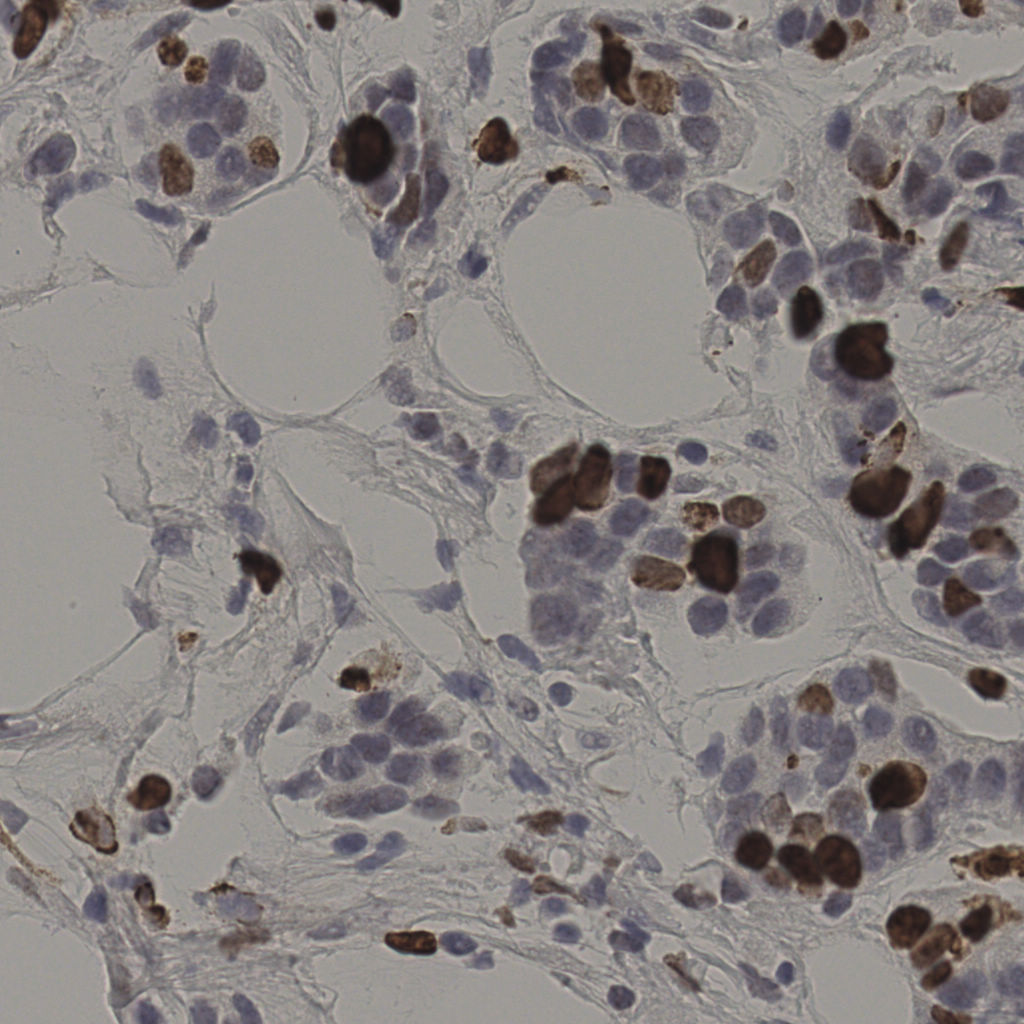

17.75%

Ki67 指数

阴 7986

阳 1723

缩略图

标记后

标记前